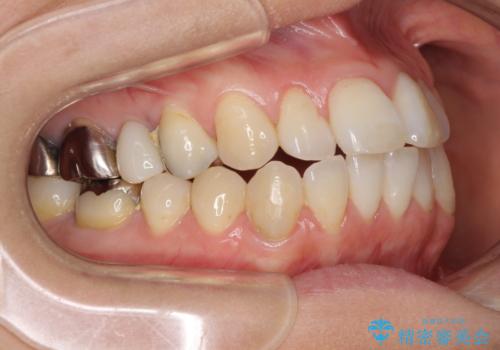

- 捻れた前歯と目立つ銀歯を気にして来院された患者様です。

歯列不正は軽微であったため、インビザライン・ライトにて改善することとしました。

左下大臼歯は根管治療が必要であったため、矯正治療前に根管治療を行い、その後矯正治療を行うこととしました。

矯正治療後には期にある銀歯を全てセラミッククラウンなどで補綴治療することとしました。

インビザライン・ライトによる矯正治療であったので、時間をかけずに治療を終えることができました。

口を開ける度に目立っていた銀歯もセラミックで自然な口元の印象となりました。